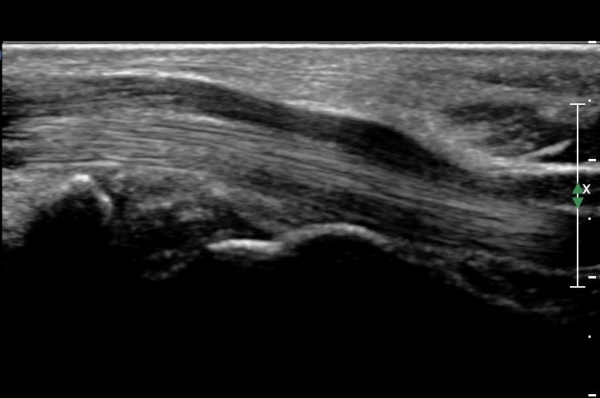

Á¤Á߽Űæ Á¾´Ü¸é°Ë»ç»ó ¼ö±Ù°ü ¸»´Ü(trapezium, capitate level) µÎ²¨¿öÁø Ⱦ¼ö±ÙÀδë(transverse carpal ligament)¿¡

ÀÇÇÑ Á¤Á߽ŰæÀÇ ±¹¼ÒÀû ¾Ð¹ÚÀÌ °üÂûµÊ(»çÁø 4, 5).